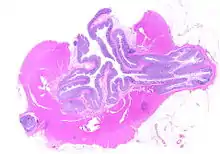

Segmental colitis associated with diverticulosis

Segmental colitis associated with diverticulosis (SCAD) is a condition characterized by localized inflammation of the colon between diverticula (interdiverticular mucosa) while sparing the diverticular orifices. SCAD may lead to abdominal pain, especially in the left lower quadrant, intermittent rectal bleeding, and chronic diarrhea.